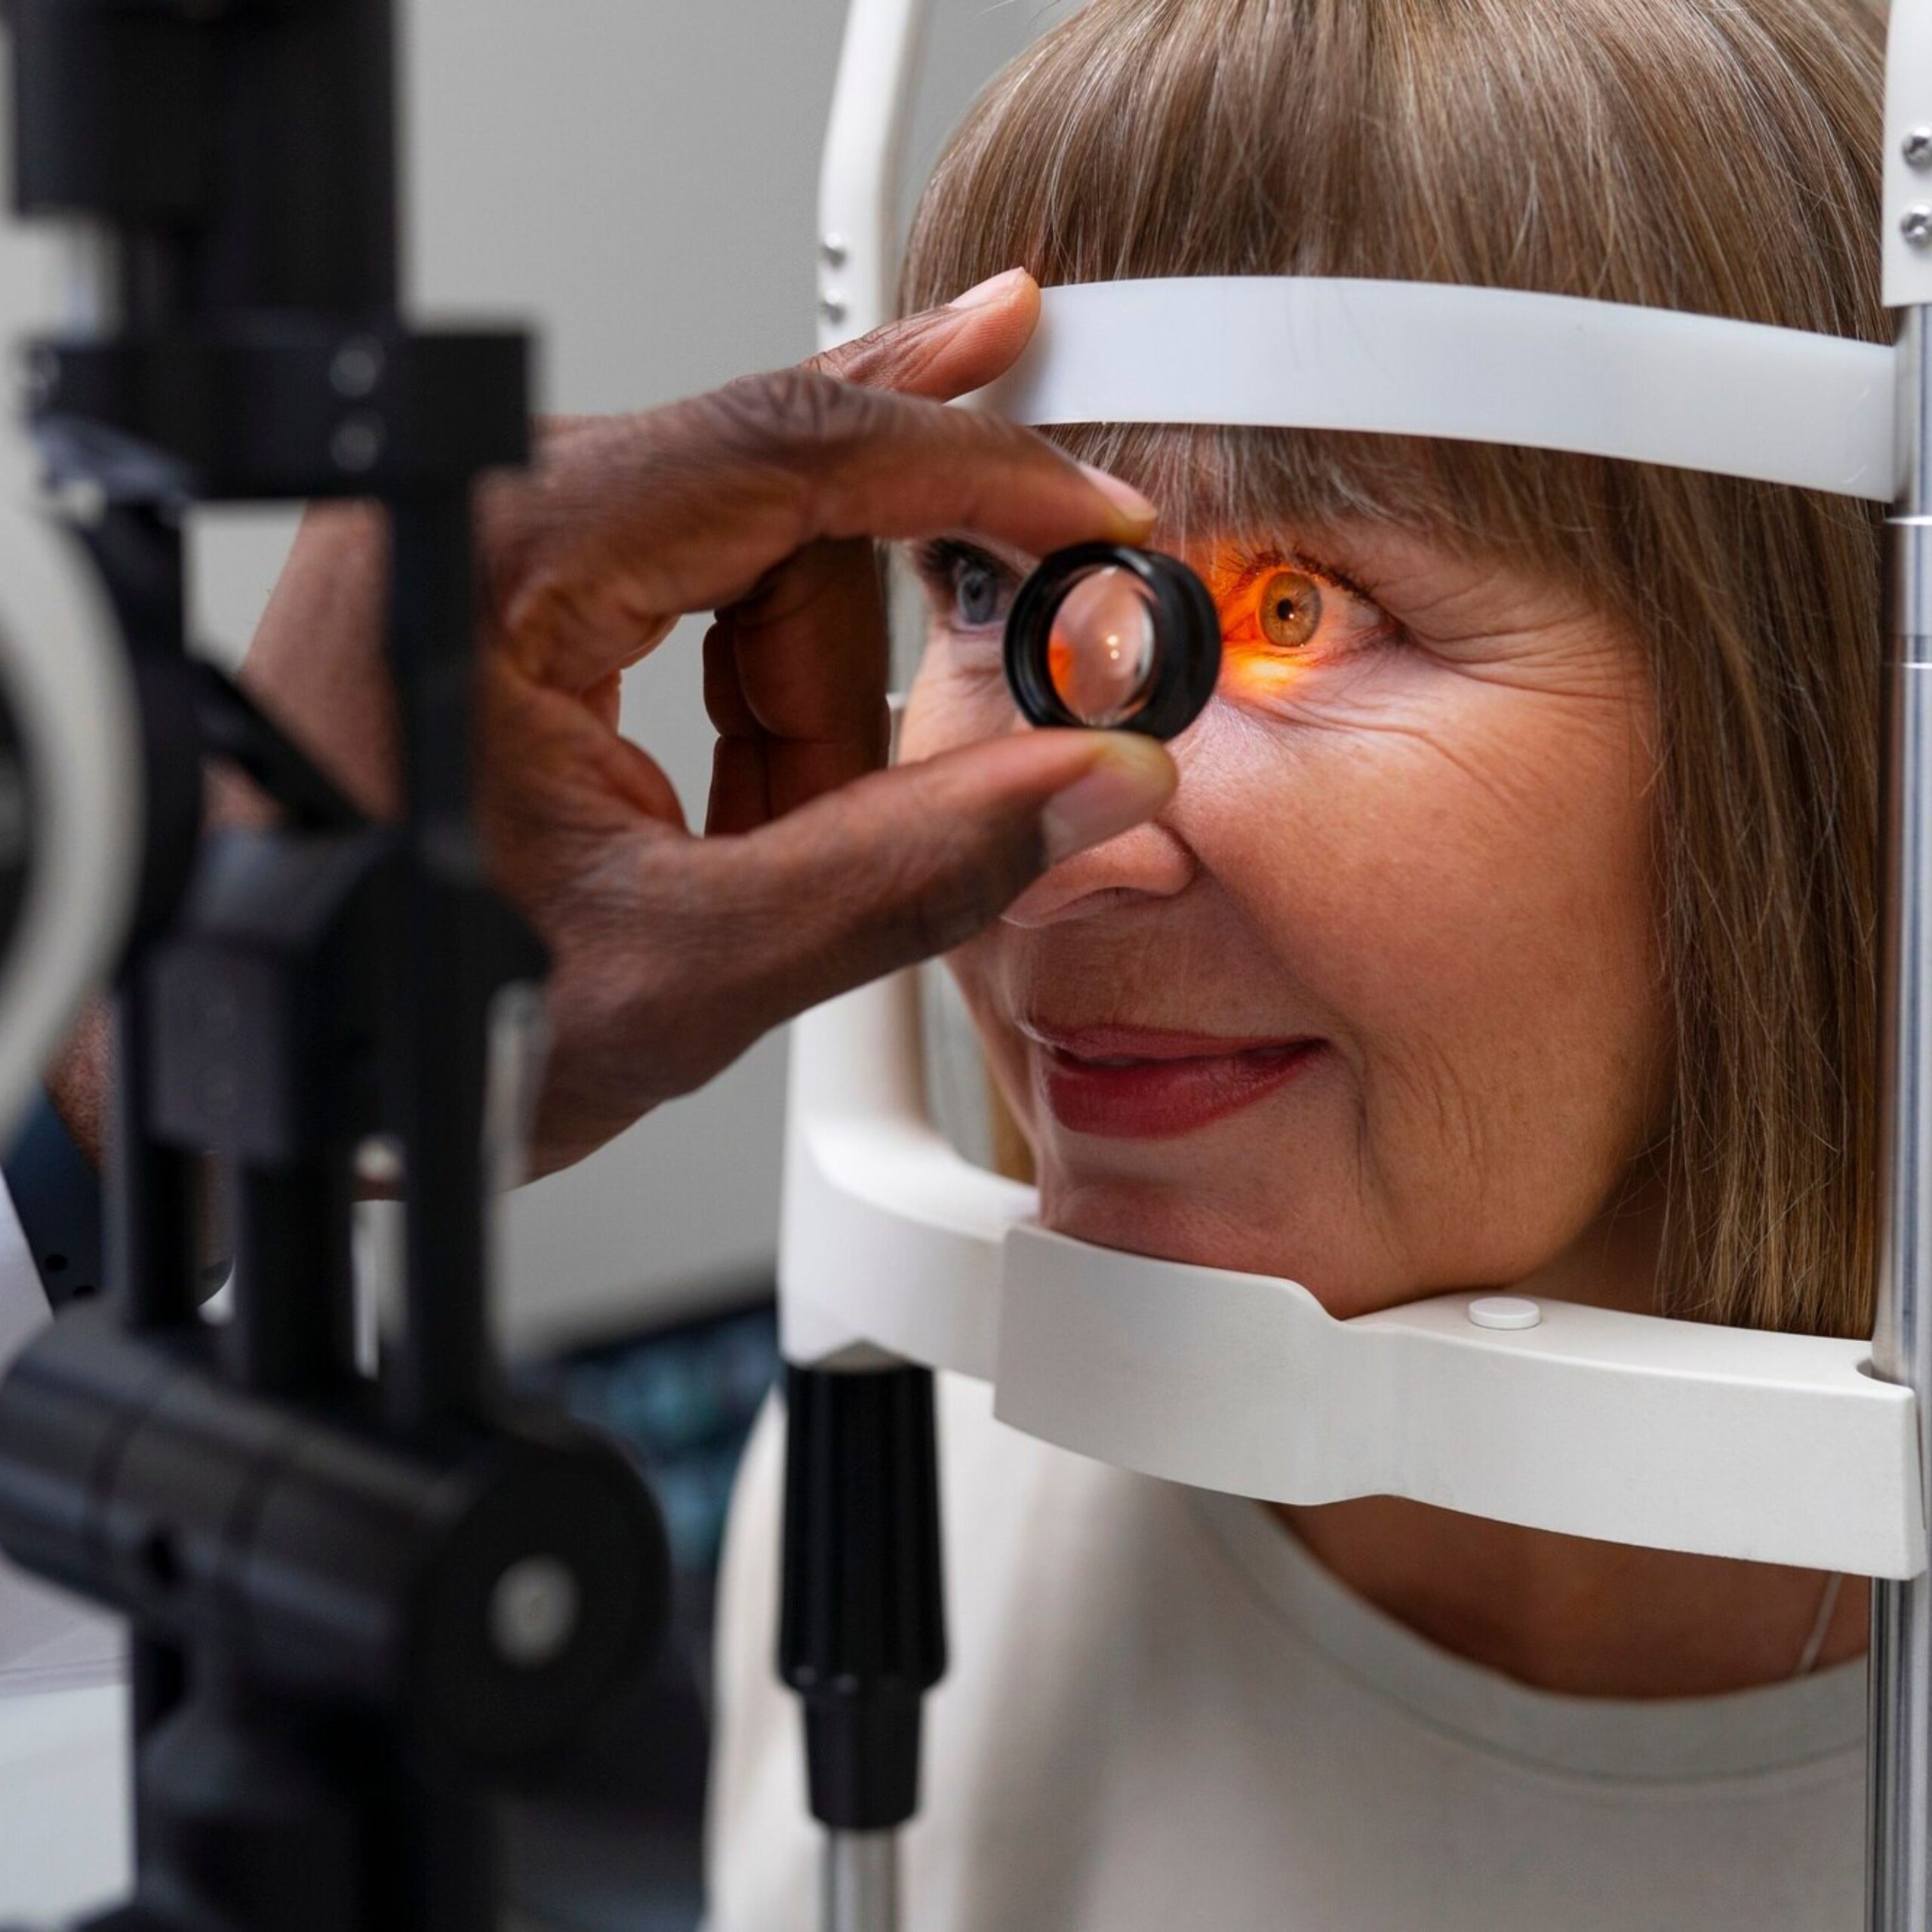

A pioneering pharmaceutical company committed to delivering high-quality ophthalmic products that improve vision and enhance the quality of life for individuals worldwide. With a focus on innovation, precision, and patient care, Protech Remedies stands at the forefront of ophthalmic pharmaceutical advancements.Our product range encompasses a comprehensive selection of ophthalmic solutions designed to address various eye conditions, from common ailments like dry eyes and infections to more complex issues such as glaucoma and cataracts. Each product is meticulously formulated using cutting-edge technology and the highest standards of quality control to ensure efficacy, safety, and comfort for our patients.